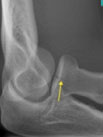

Our Hand Therapists, Physiotherapists and Occupational Therapists are experienced in reading X-rays and CT’s for elbow dislocations and they will be able to guide your treatment depending on the severity of your dislocation.

Action Rehab hand therapists can assess, advise, and treat dislocated elbows and seek specialist surgical opinion when required. Our therapists have the ability to read X-rays and CT scans and the Hand Therapist at Action Rehab can assess medical imagery deciding the most appropriate treatment plan for your elbow dislocation.

Choosing the right hand Therapist starts with them being able to read your X-rays and then fabricate the right brace for you. The therapists at Action Rehab are experienced in assessing and reading X-rays.